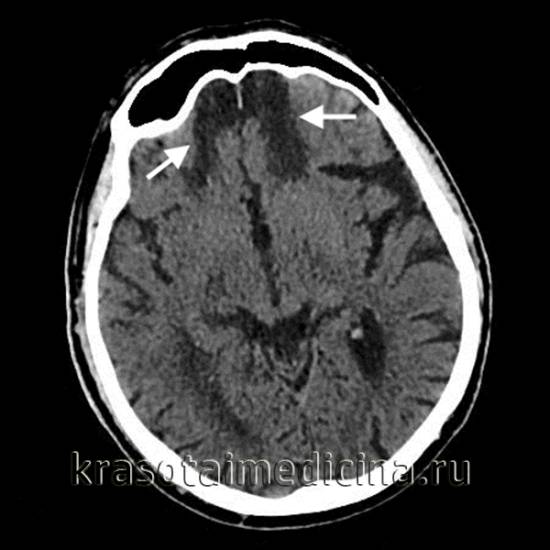

image

Использование УЗИ позволяет выявить некоторые врожденные кисты еще в период внутриутробного развития, после рождения ребенка и до закрытия его большого родничка диагностика возможна при помощи нейросонографии. В дальнейшем визуализировать кисту можно посредством КТ или МРТ головного мозга. Для дифференцировки кистозного образования от опухоли мозга эти исследования проводят с контрастированием, поскольку в отличие от опухоли, киста не накапливает в себе контрастное вещество. Для лучшей визуализации кистозной полости возможно введение в нее контраста путем пункции кисты. В отличие от МРТ, КТ головного мозга дает возможность судить о вязкости содержимого кисты по плотности ее изображения, что учитывается при планировании хирургического лечения. Основополагающее значение имеет не только установление диагноза, но и непрерывное наблюдение за кистозным образованием для оценки изменения его объема в динамике. При постинсультном генезе кисты дополнительно прибегают к сосудистым обследованиям: дуплексному сканированию, УЗДГ, КТ или МРТ сосудов головного мозга.